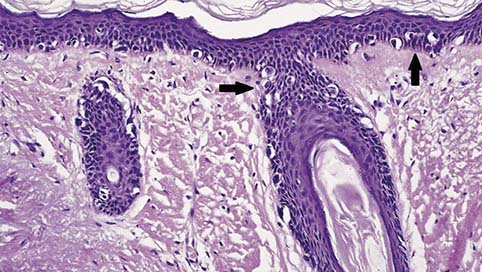

De incidentie van lentigo maligna (LM) stijgt, vooral bij ouderen. Een LM is een premaligne huidafwijking, die de vorm heeft van een onregelmatige bruine macula op de zonbeschenen huid. …